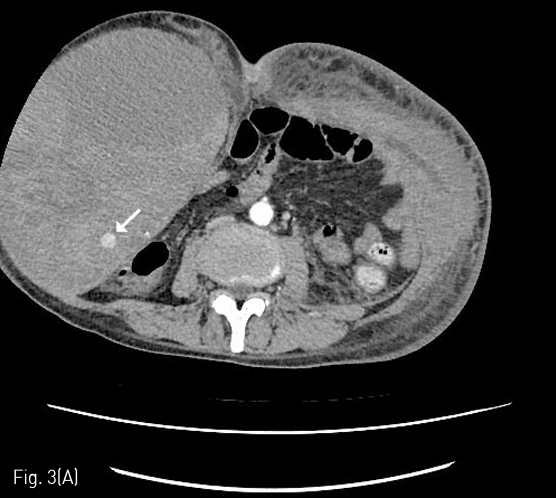

입원 중 발생한 복부와 하지의 반상출혈 및 헤모글로빈 감소로 시행한 CT에서 우측 장골회선동맥(deep circumflex iliac artery)에서의 활동성 출혈 및 우측 복벽의 혈종(13 x 9cm)이 확인되어 (Fig. 1A), Glue를 이용하여 색전술을 시행하였다(Fig. 1B). 최초 증상발생일을 기준으로 7일째 재발한 증상으로 촬영한 CT에서 혈종의 크기가 증가하였으며 (26 x 12cm), 우측 하복벽동맥(inferior epigastric artery)의 출혈병소가 관찰되어(Fig. 2A), Glue를 이용하여 2차 색전술을 시행하였다 (Fig. 2B). 다시 11일째 증상 재발하여 시행한 CT에서 혈종은 좌측 복벽에도 발생한 상태였으며 활동성 출혈병소는 우측에서만 확인되어 (Fig. 3A) 3차 응급색전술을 시행하였다. 혈관조영시 우측 장요동맥(iliolumbar artery)에서 혈관외유출이 확인되어 다시 Glue를 이용하여 색전술을 시행하였으며 (Fig. 3B), 좌측 복벽혈종의 원인 혈관은 보이지 않았다. 다시 15일째 같은 원인으로 시행한 CT에서 복벽혈종은 좌우가 연결되어 복강내 장기들을 압박하고 있었으며 크기는 약 31 x 15cm까지 커져있는 상태였고 (Fig. 4A), 좌측 서혜부에 활동성 출혈병소가 확인되어(Fig. 4B) 응급혈관조영술을 시행하였다. 혈관조영술에서 근위부 대퇴동맥과 대퇴회선 동맥(circumflex femoral artery)의 작은 분지에서 출혈병소가 확인되었으며, 각각에 대해 Gelfoam을 이용하여 색전술을 시행하였다 (Fig. 4C). 다시 같은 원인으로 26일째 CT 시행하였으며, 혈종은 더욱 커져 약 34 x 18cm까지 커지고 (Fig. 5A), 배꼽 근방에서는 피부 결손이 발생하였으며, 복강내 장기의 압박으로 양측 수신증까지 발생한 상태였다. 좌측 하복벽동맥에서 기시하는 출혈병소가 의심되었기에 다시 혈관조영술을 시행하였으며, 해당 동맥에 대해 Gelfoam을 이용하여 색전술을 시행하였다 (Fig. 5B). 추가적으로 좌측 대퇴동맥 카테터 삽입부에 가성동맥류가 형성된 것이 확인되었고 보존적으로 추적관찰하기로 하였다. 최초 색전술을 기준으로 29일째 6번째 CT를 촬영하였으며, 우측 상복벽에 새롭게 출혈병소가 확인되었다 (Fig. 6A). 다시 혈관조영술을 시행하였으며, 우측 내흉동맥에서 기시하는 근횡격막동맥 (musculophrenic artery)의 분지에서 출혈병소가 확인되어 Glue를 이용하여 색전술을 시행하였다 (Fig. 6B).

Fig 3A

(A) 4 days later, more size increase and another active bleeding focus of the right abdominal wall hematoma were noted on follow-up abdomen CT. New hematoma at left side of the abdominal wall without any definite detected bleeding focus on the CT scan.

Fig 3B

(B) Extravasation of contrast media from the iliolumbar artery of the posterior division of the right internal iliac artery was successfully treated with glue embolization.